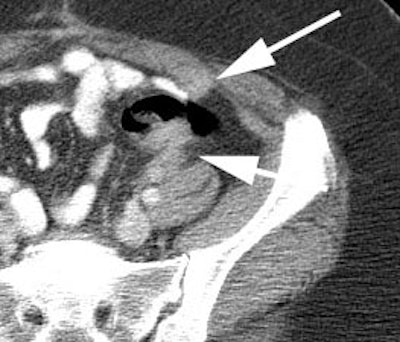

Initial staging for colorectal carcinoma: The patient below presented for evaluation of colorectal carcinoma. The CT scan demonstrated a large liver mass (red arrows) compatible with metastatic disease. The patient's cecal mass (black arrow on PET scan) was not detected on the CT study (white arrow). No other lesions were identified on the PET scan. |

|